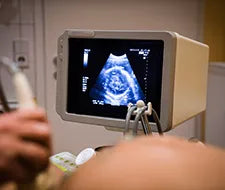

In unserem Schwangerschaftskalender fassen wir für dich zusammen, welche Entwicklungsschritte dein Baby in dieser Woche durchläuft und zeigen dir, wie groß und schwer es inzwischen ist. Dabei erläutern wir dir auch, wie sich dein Körper in der SSW 21 entwickelt und welche Symptome du möglicherweise hast. Wir fassen zudem zusammen, was dich bei der zweiten großen Ultraschalluntersuchung erwartet und wieso du dir schon jetzt unsere Federwiege anschauen solltest.